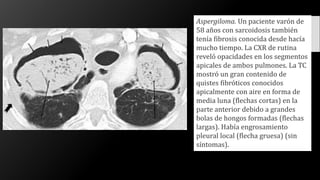

Aspergiloma. Un paciente varón de

58 años con sarcoidosis también

tenía fibrosis conocida desde hacía

mucho tiempo. La CXR de rutina

reveló opacidades en los segmentos

apicales de ambos pulmones. La TC

mostró un gran contenido de

quistes fibróticos conocidos

apicalmente con aire en forma de

media luna (flechas cortas) en la

parte anterior debido a grandes

bolas de hongos formadas (flechas

largas). Había engrosamiento

pleural local (flecha gruesa) (sin

síntomas).